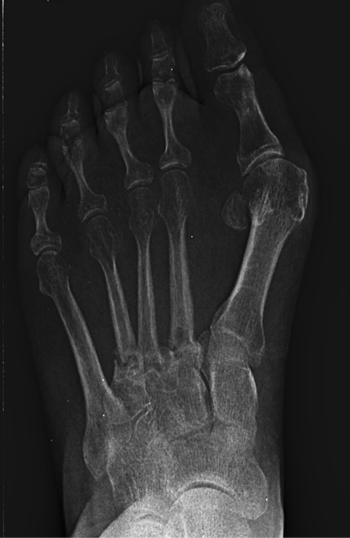

Se realizó radiografía dorso-plantar en carga del pie derecho (Figura 1) que mostraba una imagen radiológica compatible con ausencia de consolidación de las osteotomías en las bases de 2.º, 3.º y 4.º metatarsianos, además de la presencia de hallux abductus valgus. Se solicitó una tomografía axial computarizada (TAC) para estudiar más detenidamente el estado actual del proceso de consolidación ósea. La paciente acudió con resultado de TAC el 5 de mayo de 2015, donde se evidenció la ausencia completa de consolidación ósea en segundo metatarsiano (Figuras 2A y 2B), consolidación prácticamente completa de tercer metatarsiano (Figura 2C) y la presencia de callo óseo con consolidación incompleta en el cuatro metatarsiano (Figura 2D).

Figura 1. Radiografía dorso-plantar en carga del pie derecho. Se evidencia la ausencia de consolidación de las osteotomías en las bases de 2.º, 3.º y 4.º metatarsianos después de 9 meses de la intervención inicial.

Se diagnosticó entonces de pseudoartrosis en segundo metatarsiano y de retraso de la consolidación en cuarto metatarsiano, además de la deformidad de hallux abductus valgus. Se explicaron a la paciente las opciones de tratamiento conservador basado principalmente en reposo, magnetoterapia y posibles infiltraciones de plasma rico en plaquetas y de tratamiento quirúrgico. Como tratamiento quirúrgico se le propuso en el segundo metatarsiano la limpieza de la pseudoartrosis, colocación de autoinjerto corticoesponjoso (obtenido de calcáneo) para dotar de soporte estructural y mantener la longitud del metatarsiano, y estabilización con placa dorsal. Además, se propuso estabilizar el cuarto metatarsiano mediante el uso también de placa dorsal para asegurar su no evolución hacia pseudoartrosis y corregir la deformidad en hallux abductus valgus. La paciente desestimó el tratamiento conservador, solicitando tratamiento quirúrgico, y se realizó preoperatorio con analítica sanguínea, electrocardiograma y consulta preoparatoria con anestesista.